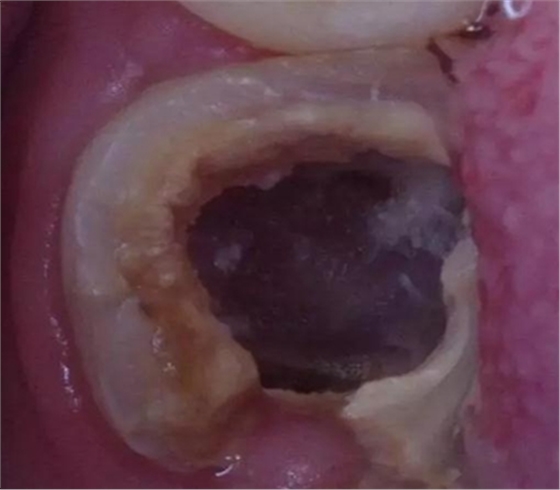

因為腐質(zhì)比較多用剔挖器處理:

剔挖器進一步處理后見到底穿部位:根管挖匙派上用場,穿孔部位有少許膿液。